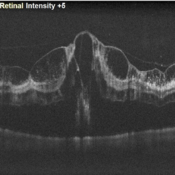

Garland of Superficial Infarct on OCT

OCT of 78 year-old hypertensive male with multiple soft exudates over posterior pole on clinical examination.

Photographer: Prashant Bawankule, Sarakshi Netralaya, Nagpur, Maharashtra , India

Imaging device: Mirante ( by Nidek)

Condition/keywords: Hypertensive retinopathy, Superficial infarcts